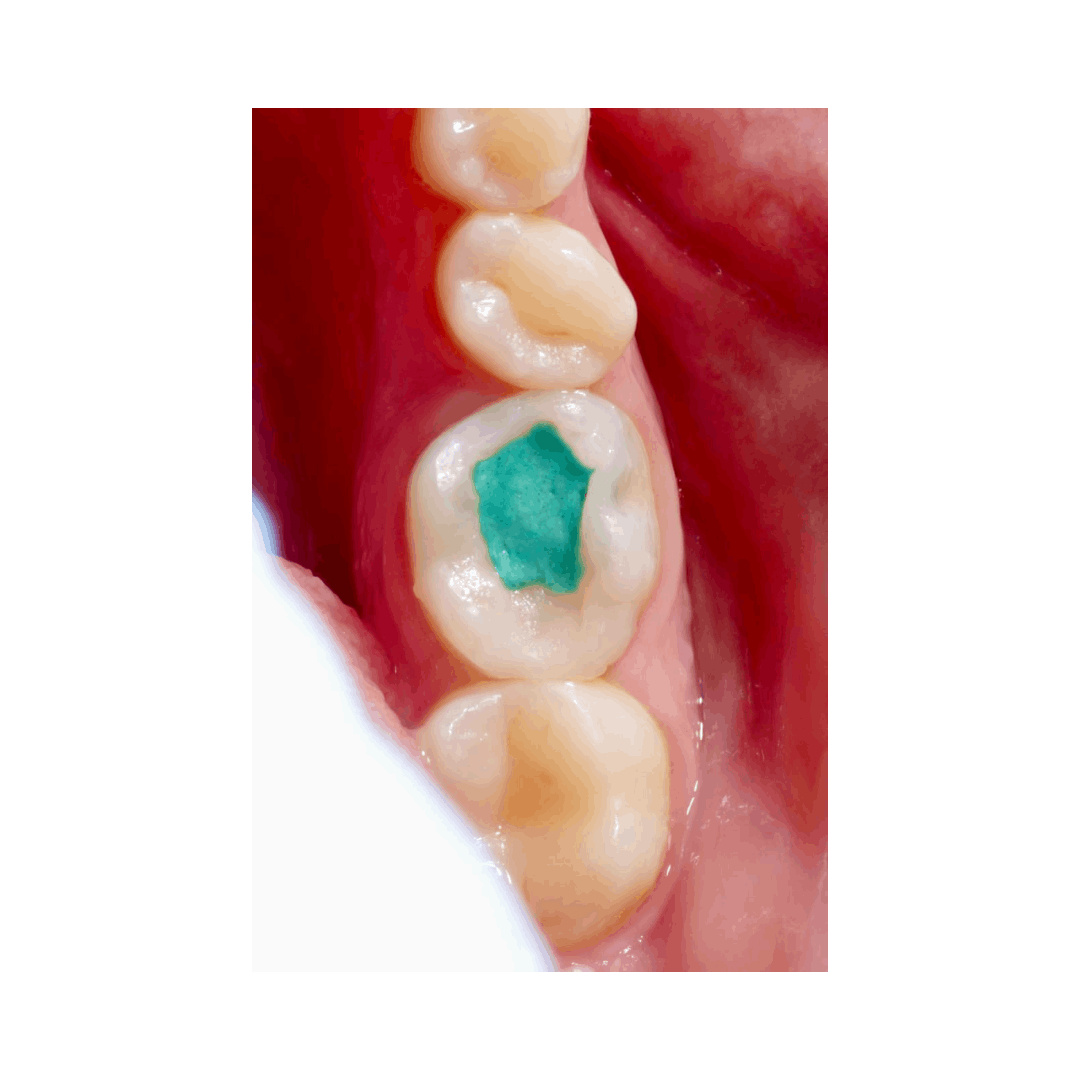

Реферативный пациент, пульпит зуба 36.

Попытки самостоятельно достать фрагмент привели к перерасширению.